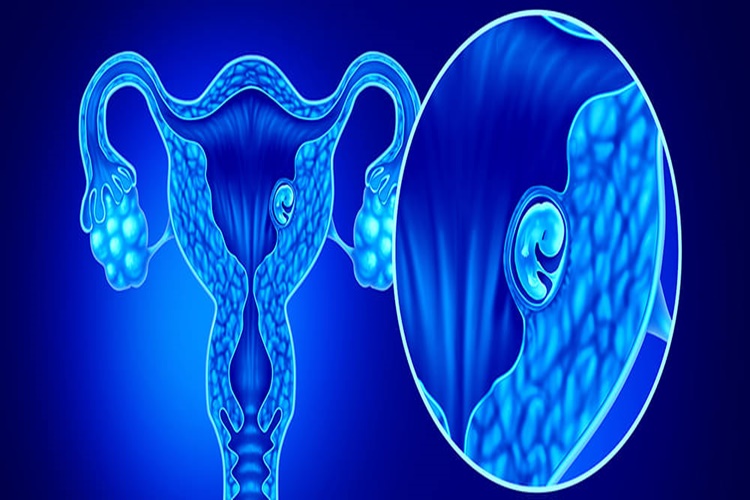

7. Hormonal Değişiklikler: Hamilelik veya menstrüasyon gibi hormonal değişiklikler, vücutta sıvı tutulumuna neden olarak ayak bileğinde şişliğe yol açabilir.

7. Hormonal Değişiklikler: Hamilelik

veya menstrüasyon gibi hormonal değişiklikler, vücutta sıvı tutulumuna neden

olarak ayak bileğinde şişliğe yol açabilir.